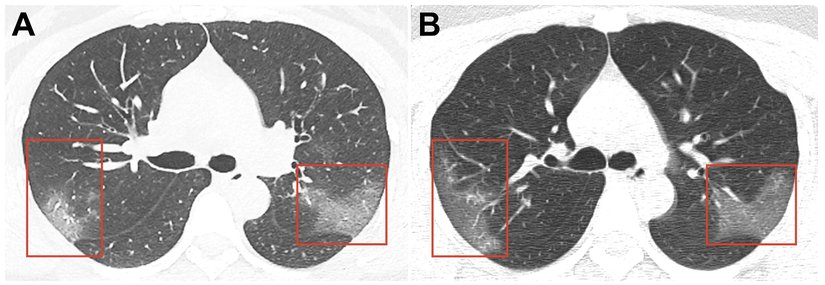

Mevcut koronavirüs hastalarının akciğer taramalarında, sıvının akciğerlerde biriktiği ve beyaz lekeler olarak göründüğü bir durum olan "buzlu cam (ING: ground glass)" görünüyor.

Aşağıdaki taramalar, farklı zamanlarda aynı hastadan alınmış. Kişinin akciğerindeki "buzlu cam"ın hastalık ilerledikçe daha da belirginleştiği görülüyor.

İlk bulgular, nefes darlığına geçen sürenin 5 gün, hastaneye başvurmaya kadar geçen sürenin 7 gün, Akciğer Solunum Yetmezliği bulgularına kadar geçen süre 8 gün, YBÜ yatışa kadar geçen süre 10 gün olduğunu gösterdi. Hastaların çoğunun hastaneye yatış sırasında çekilen Akciğer Bilgisayarlı Tomografilerinde; çift taraflı buzlu cam alanları ve yama şeklinde tutulum vardı.